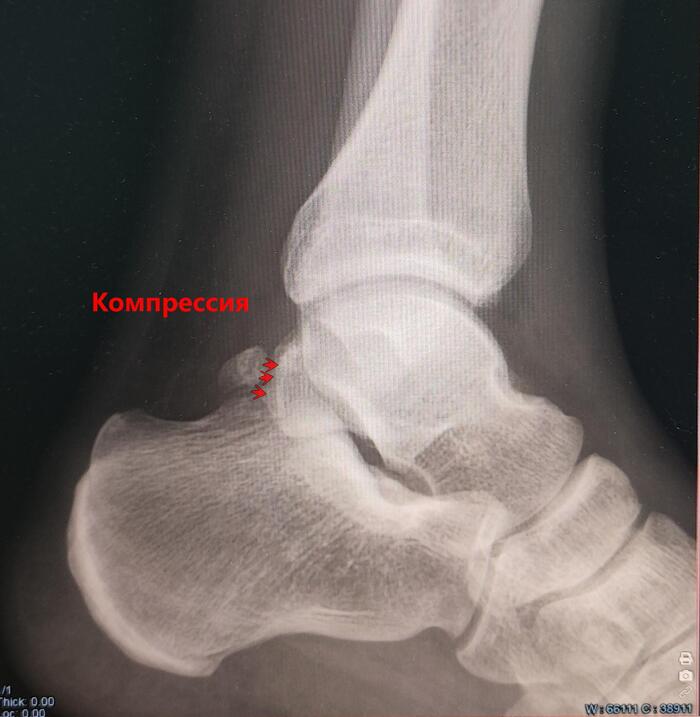

Треугольная кость таранной кости(Os trigonum)

Os trigonum — это анатомический вариант развития стопы/аномалия развития, представляющая собой отдельную костную структуру, расположенную кзади от таранной кости.

• Формируется из не слившегося вторичного центра окостенения таранной кости

• Встречается у 5–15% населения, часто двусторонне.

• Может быть бессимптомной или вызывать боль при физических нагрузках, занятии спортом.

• Может вызывать задний импиджмент голеностопа — боль при тыльном сгибании стопы.

Из анамнеза-боли в левом голеностопном суставе при занятии спортом.

Описание: на Р-граммах левого гс/с в 2х проекциях суставная щель не сужена, субхондральный склероз, краевые остеофиты-не выявлены. По заднему контуру таранной кости определяется наличие дополнительной кости-os trigonum. Заключение:Os trigonum(аномалия развития левой стопы), наиболее вероятно вызывающая синдром компрессии таранной кости.

Категория годности с диагнозом Os trigonum(аномалия развития левой стопы), наиболее вероятно вызывающая синдром компрессии таранной кости-по статье 69г Б3-годен к военной службе с незначительными ограничениями.